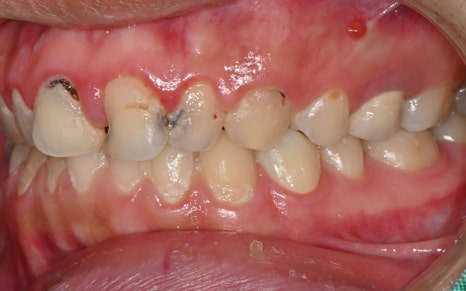

This is what it looked like after some of the treatment had been completed.

The most noticeable change was,

above all, the aesthetic restoration of the front teeth.

Looking at the before-treatment photos,

the front teeth had large cavities and damage

to the point that it was hard to smile,

and the areas filled with resin here and there

were also a major source of aesthetic stress.

But the post-treatment photos

feel like a completely different person.

As if the teeth had originally been pretty and straight,

the color looks natural,

and the shape was restored to fit the face perfectly.

In fact, the patient said,

“This really feels like my original tooth,

and it doesn’t look like I had any treatment at all,” and expressed satisfaction.